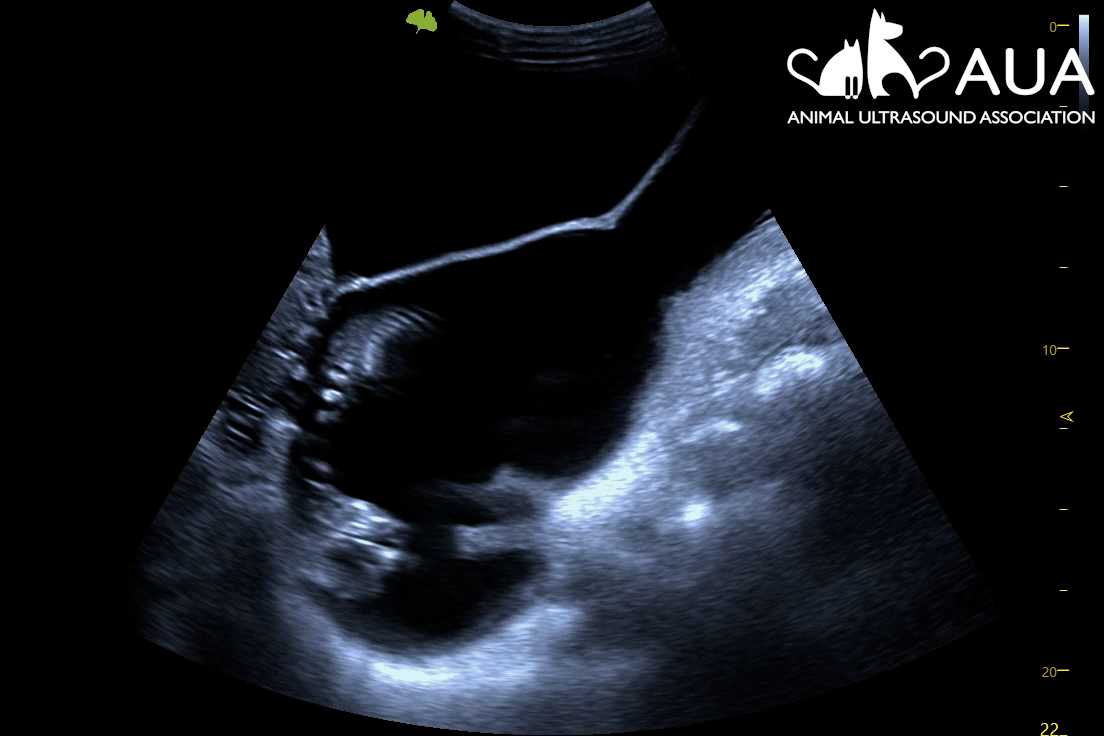

Nala came for her pregnancy scan today. We saw at least 6 (probably 7) foetuses, at around six weeks of gestation.